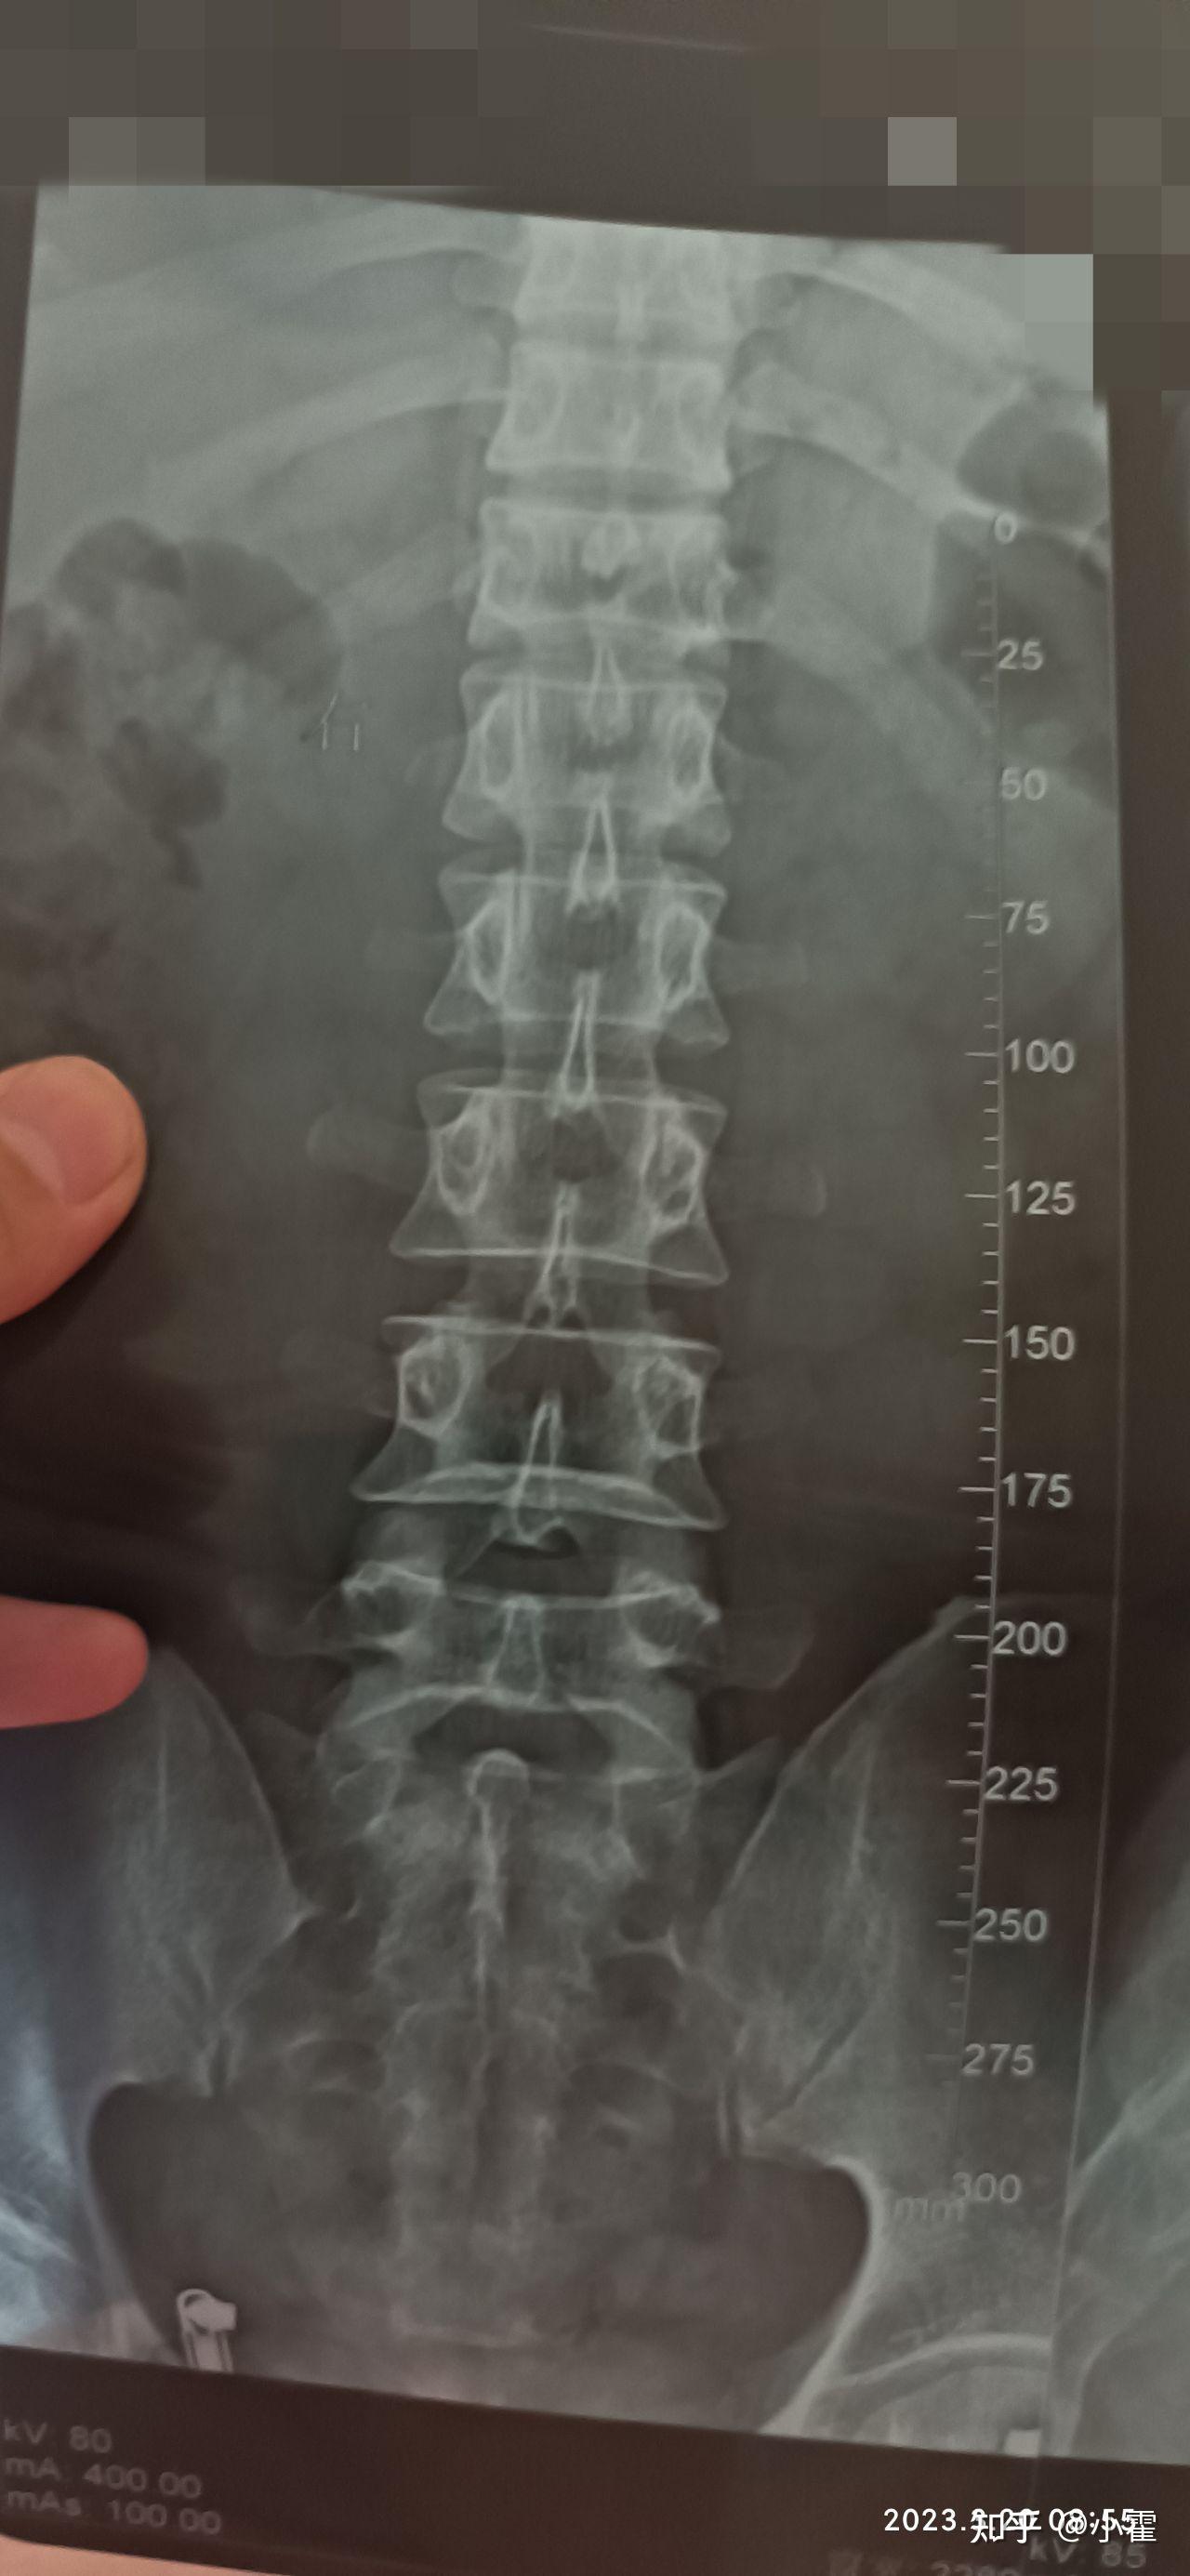

4、二症状主要症状为背痛受伤后立即出现,活动时加重脊柱畸形如脊柱后凸畸形,即驼背及神经症状骨折块压迫神经时,可能出现下肢无力麻木大小便失禁等三诊断诊断需结合病史询问受伤经过及既往病史体格检查脊柱压痛叩击痛及活动度影像学检查X线初步判断骨折,CT和MRI。

10、胸椎压缩性骨折的严重程度需结合骨折类型压缩程度及神经损伤情况综合判断1 压缩程度是核心指标轻度压缩椎体高度丢失小于13通常不会破坏脊柱稳定性,患者可能仅表现为局部疼痛,无神经功能障碍此类情况通过保守治疗如卧床休息支具固定药物镇痛即可恢复,预后良好但若压缩超过13或椎体后壁破裂,可能引发脊柱。

11、胸椎压缩性骨折是脊柱骨折的一种类型,特指胸椎椎体因外力作用发生高度降低的骨折其核心机制与胸椎的解剖结构和力学特点密切相关1 解剖基础与力学原理胸椎由12节椎体组成,其生理曲度为前突向前凸出,而相邻的腰椎曲度为后突向后凸出在胸腰段胸椎与腰椎交界处,两种相反曲度交汇,形成。

14、十二胸椎压缩性骨折是一种以胸椎体高度降低为特征的脊柱损伤,需从病因症状诊断治疗及预防等方面综合管理一病因主要分为外力冲击与骨质疏松两类外力冲击包括跌倒车祸重物砸伤等直接暴力,导致椎体前部或中部受压变形骨质疏松则多见于老年人或长期激素治疗者,骨密度降低使椎体更易因轻微。